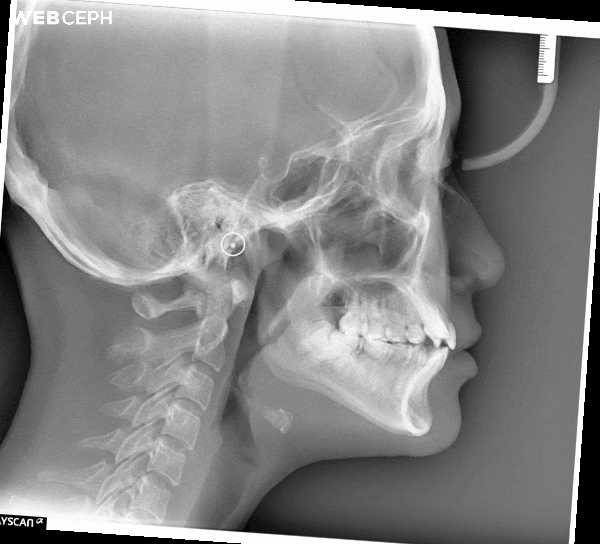

透過 Bjork 分析法(Bjork Analysis) 評估後發現,小庭屬於 低角型顱顎骨格模式(Hypodivergent Skeletal Pattern),外觀上可見臉型略短的特徵。此外,她的 上下門牙夾角偏小(呈銳角),使得前牙外傾的情況較為明顯

Through Bjork Analysis, we found that Ting had a hypodivergent skeletal pattern, characterized by a shorter lower facial height. The analysis also revealed a reduced interincisal angle, causing her front teeth to appear slightly flared.

在治療規劃上,我們希望藉由調整上門牙的軸向,使其角度回復至理想位置,進而改變 下顎平面角度(Mandibular Plane Angle) 與 咬合平面角度(Occlusal Plane Angle)。這樣的改變有助於讓臉部比例回復至較接近 正常顱顎關係(Normal Divergent Skeletal Pattern) 的狀態。

In planning her treatment, Dr. Ko aimed to upright the maxillary incisors and bring them back to a more ideal inclination. This adjustment would also help refine both the mandibular plane angle and the occlusal plane angle, restoring her facial proportions toward a more balanced skeletal pattern.

同時,適度增加咬合平面角度,可在微笑時創造更自然的 微笑曲線(Smile Arc) 與理想的 露齒量(Incisal Show),使整體笑容更具協調與美感。

By slightly increasing the occlusal plane angle, Dr. Ko sought to enhance Ting’s smile arc and achieve a more natural incisal show, allowing her smile to look both harmonious and effortlessly confident.